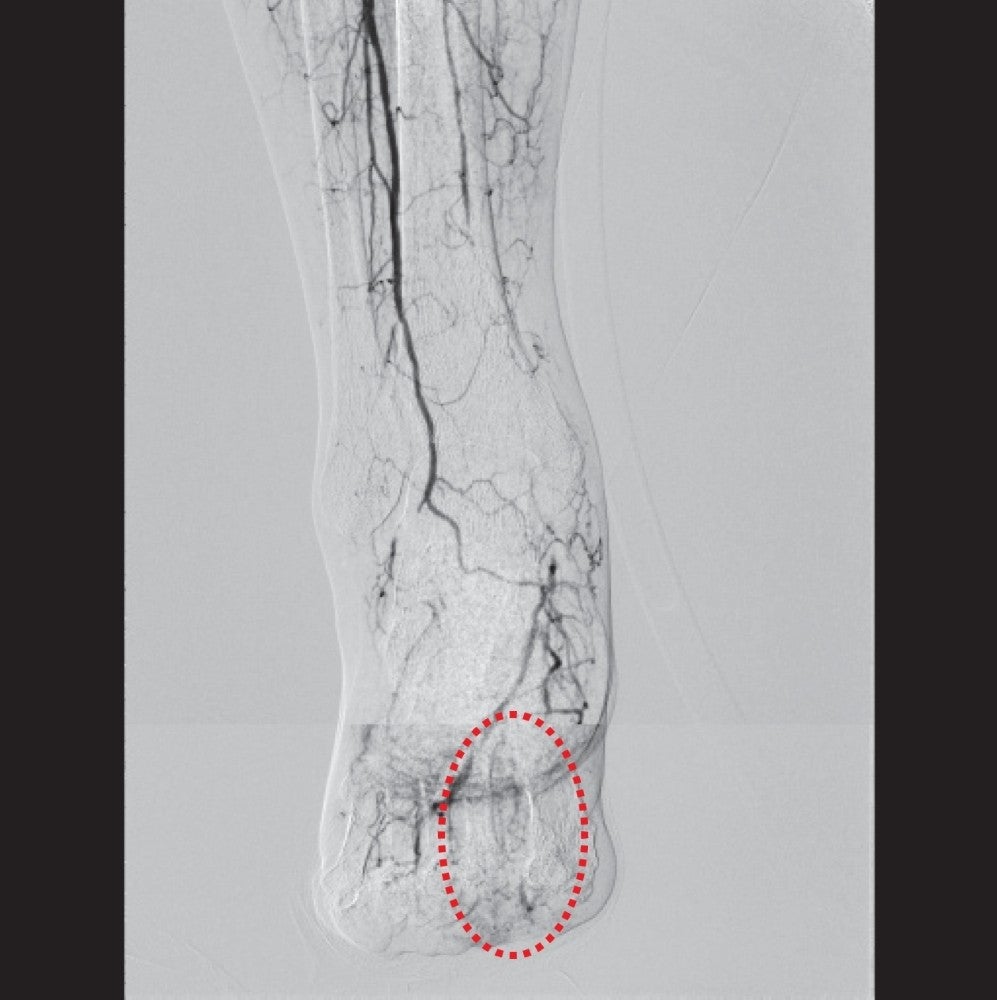

CFAおよびIliac領域治療後のSFA造影所見と石灰化の撮影では、閉塞長自体は150 mm程度だが、石灰化を伴う狭窄が連続しており、全体の病変長としては280 mmであった(図3)。